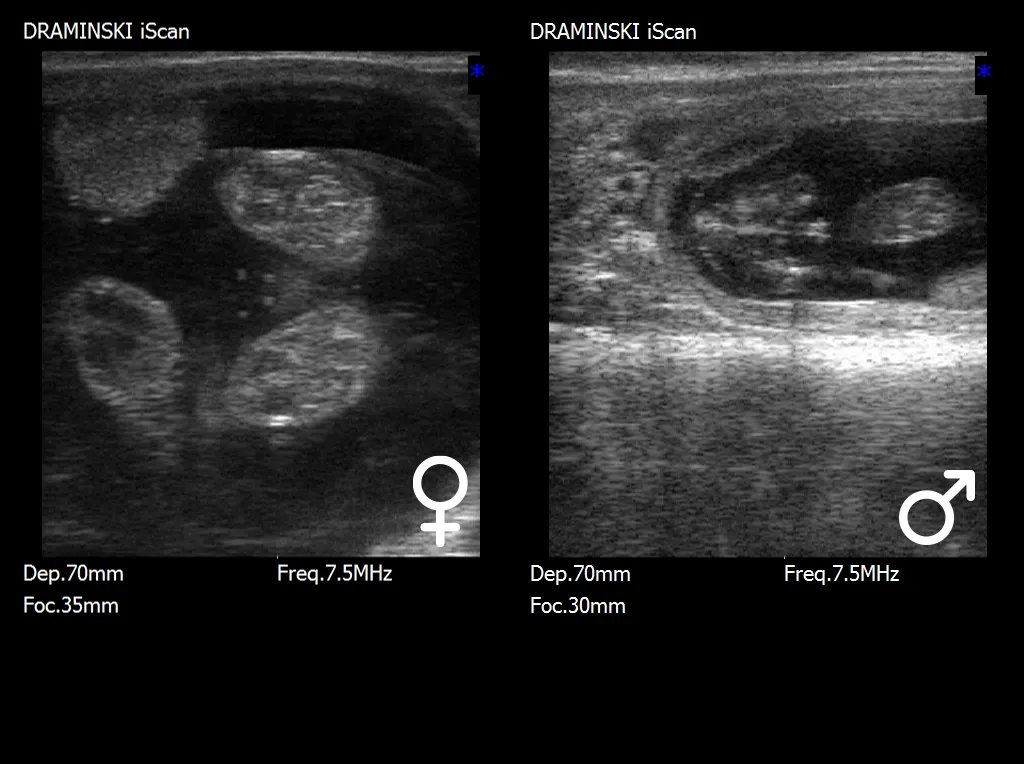

W tym etapie rozwoju kluczową strukturą diagnostyczną jest guzek płciowy (tuberculum genitale), który ulega charakterystycznemu przemieszczeniu w zależności od płci. U płodów męskich guzek płciowy przemieszcza się w kierunku pępka i przyszłego prącia, natomiast u płodów żeńskich lokalizuje się bliżej ogona, w rejonie przyszłego sromu. Prawidłowa interpretacja położenia tej struktury wymaga nie tylko dobrej jakości obrazu ultrasonograficznego, lecz także odpowiedniego doświadczenia badającego, ponieważ niewielkie różnice w ułożeniu płodu mogą wpływać na ocenę.

W późniejszym okresie ciąży, po około 70.–80. dniu, możliwa jest identyfikacja bardziej wykształconych narządów płciowych, takich jak moszna u płodów męskich lub struktury sromu u płodów żeńskich. Choć w tym czasie cechy płciowe są bardziej widoczne, to jednocześnie badanie staje się trudniejsze ze względu na zwiększające się rozmiary płodu, jego głębsze położenie w jamie macicy oraz ograniczoną możliwość manewrowania głowicą ultrasonograficzną.